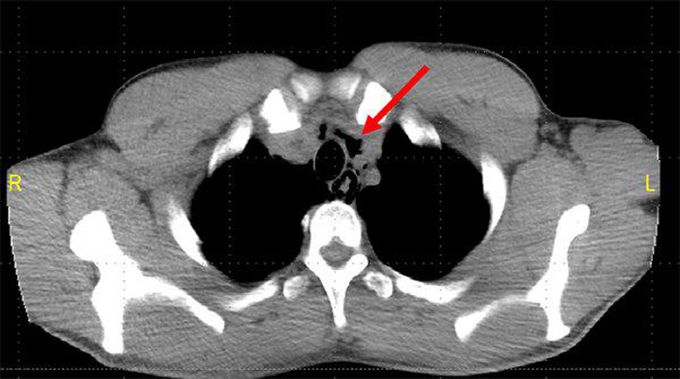

Esophageal perforation broadly classifies into spontaneous and iatrogenic causes. Iatrogenic perforation is more common. It may occur while performing diagnostic or therapeutic endoscopy. Spontaneous perforation occurs during Boerhave syndrome. It may also occur while defecation, labor, or weightlifting. Reference: Bailey and Love's Short Practice of Surgery Image via: https://www.google.com/url?sa=i&url=https%3A%2F%2Fwww.emra.org%2Femresident%2Farticle%2Fmed-induced-esophageal-perforation%2F&psig=AOvVaw2r2dVkWL1zPjlWg_M5vU14&ust=1644770409778000&source=images&cd=vfe&ved=0CAwQjhxqFwoTCNC40KnN-vUCFQAAAAAdAAAAABAJ